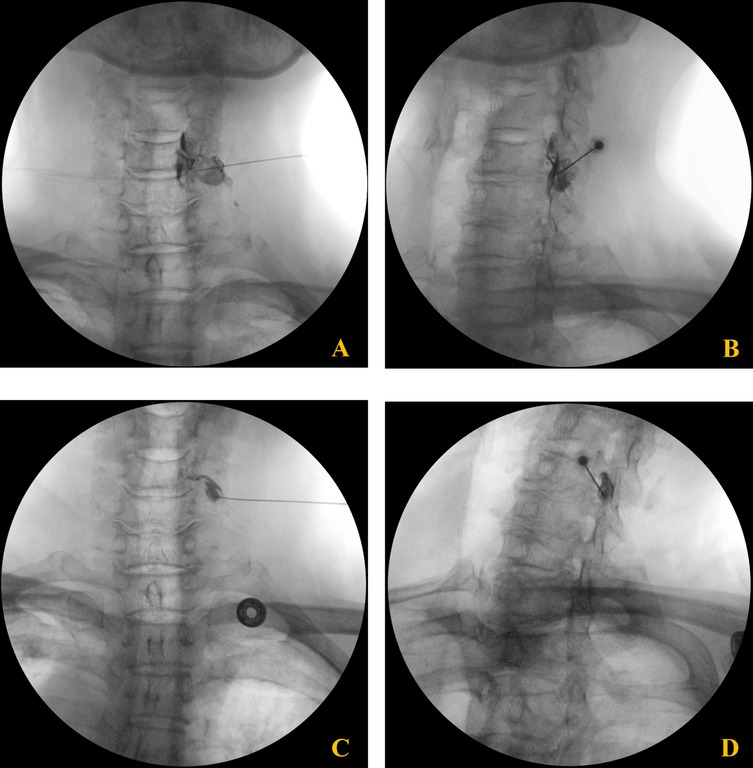

Over a five-week period, the patient received four epidural steroid injections under C-arm fluoroscopic guidance. The interlaminar approach was performed at the C6–7 level using a paramedian technique, directing the needle toward the right side for optimal drug delivery. The transforaminal approach targeted the right C6 nerve root by advancing the needle toward the C5/6 intervertebral foramen (Figure 2). Each injection consisted of dexamethasone palmitate (4 mg) (13), hyaluronidase (1,500 IU) (14), and 0.1% lidocaine (5 mL) (15). The patient was evaluated at regular intervals (4 days, 2 weeks, 4 weeks, and 5 weeks), with assessments of motor strength, shoulder ROM, and subjective symptom improvement. The clinical course, including changes in muscle strength and range of motion, is summarized in Table 1.

Figure 2

Fluoroscopic images of C6 cervical transforaminal epidural steroid injection. (A,B) Anteroposterior (A) and oblique (B) views of the second injection showing needle placement and contrast spread at the C6 neural foramen. (C,D) Anteroposterior (C) and oblique (D) views of the third injection demonstrating proper needle positioning and contrast distribution along the C6 nerve root pathway.